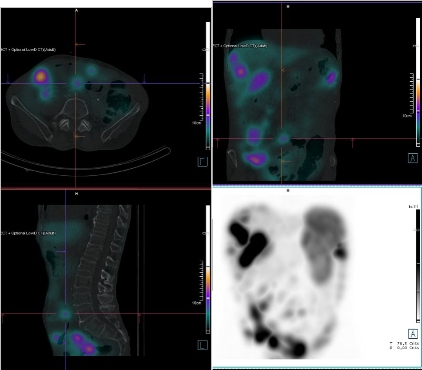

/ Obr. č. 8: Fúze SPECT/CT břicha a pánve 24 hod. po aplikaci OctreoScanu.

/

/ Obr. č. 9: Fúze SPECT/CT břicha a pánve 24 hod. po aplikaci OctreoScanu.

/ Obr. č. 10: Fúze SPECT/CT břicha a pánve 24 hod. po aplikaci OctreoScanu.

Pozorujeme patologicky zvýšenou depozici radiofarmaka: nejméně čtyři ložiska v pravém jaterním laloku (ložisko s vysokou akumulací laterálně, největší ložisko vysoce akumulující oválného tvaru dorzokaudálně, další dvě malá dorzolaterálně a kraniálně), vícečetná drobná ložiska v břiše a pánvi, zřejmě v uzlinách mezenteria a na peritoneu, ložisko pod dolním okrajem sleziny.

Akumulace dále ve slezině, ledvinách a střevních kličkách představuje fyziologickou distribuci. Vedl. nález obrovská hydronefróza pravé ledviny bez akumulace.

Mnohočetná ložiska patol. depozice Octreotidu odpovídají generalizaci procesu v dutině břišní - játra, mezenterium, karcinomatoza peritonea, pod slezinou.